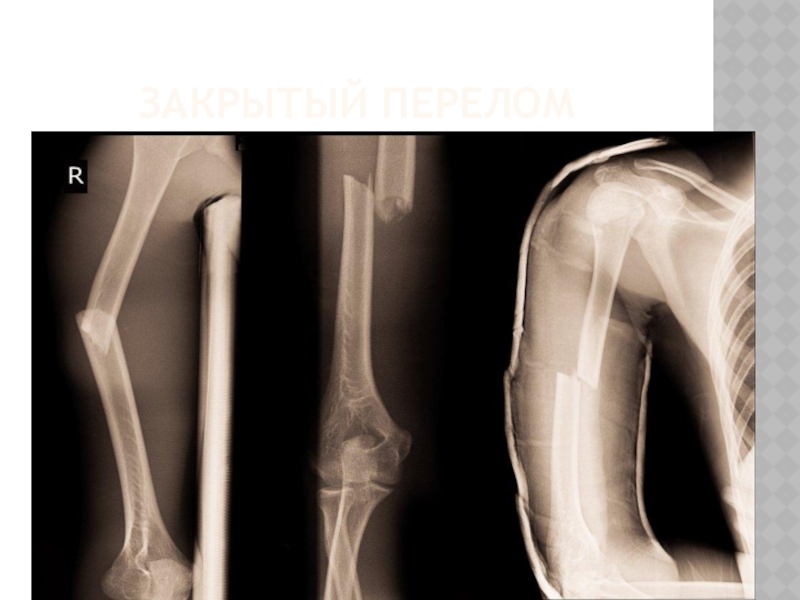

Слайд 17ЗАКРЫТЫЙ ПЕРЕЛОМ

ЗАКРЫТЫЙ ПЕРЕЛОМ

Слайд 18СИМПТОМЫ

Патологическая подвижность. Конечность становится подвижной в том месте, где в норме

она неподвижна, то есть там, где нет суставов. Конечность принимает неестественное положение , костный хруст.

Боль, отечность, гематома

СИМПТОМЫПатологическая подвижность. Конечность становится подвижной в том месте, где в норме она неподвижна, то есть там, где